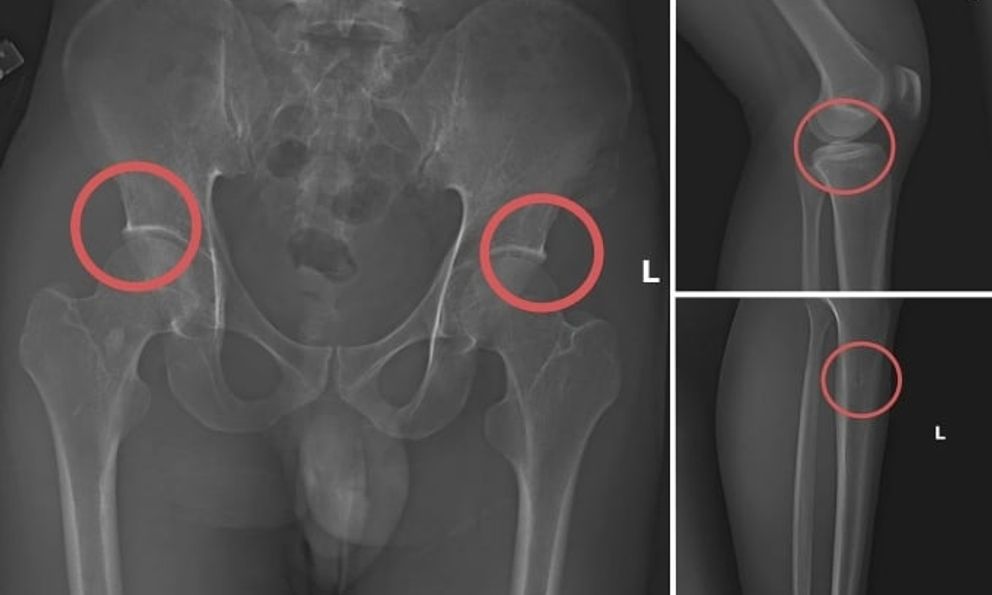

Trước đó, vụ án được cơ quan điều tra phát hiện sau khi tiến hành thu thập tài liệu liên quan. Tạ Minh Châu (30 tuổi, cựu cán bộ Trung tâm Y tế huyện Cẩm Khê – Phú Thọ) được xác định là chủ mưu, kẻ cầm đầu. Châu lợi dụng kinh nghiệm lâu năm trong ngành y, am hiểu cấu tạo xương và cơ chế chi trả bảo hiểm đối với thương tích gãy xương nên đã dựng lên một quy trình trục lợi bảo hiểm bài bản.

Đường dây này được tổ chức từ việc vận động người dân mua bảo hiểm, gây thương tích nhân tạo, cho đến hợp thức hồ sơ bệnh án để chiếm đoạt tiền. Khi thương tích đã được tạo ra, Châu cùng đồng phạm dựng hiện trường giả, từ điện giật đến trượt chân ngã suối, nhằm hợp pháp hóa hồ sơ yêu cầu chi trả.

Với thủ đoạn tinh vi này, nhóm đối tượng đã chiếm đoạt hơn 6 tỷ đồng từ nhiều công ty bảo hiểm nhân thọ. Hành vi này không chỉ vi phạm pháp luật mà còn đặt nạn nhân vào tình trạng nguy hiểm, có thể ảnh hưởng lâu dài đến sức khỏe, khả năng vận động và chất lượng sống.